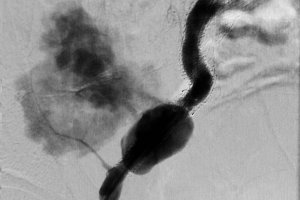

В неотложном порядке выполнена КТ – ангиография, по результатам которой определялся разрыв аневризматически измененной наружной подвздошной артерии в области установленного ранее стента, забрюшинная гематома.

В экстренном порядке выполнено эндопротезирование наружной подвздошной артерии баллонорасширяемым стент-графтом Advanta V12 9х58 мм.